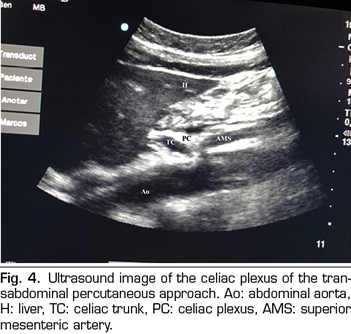

Figure 4